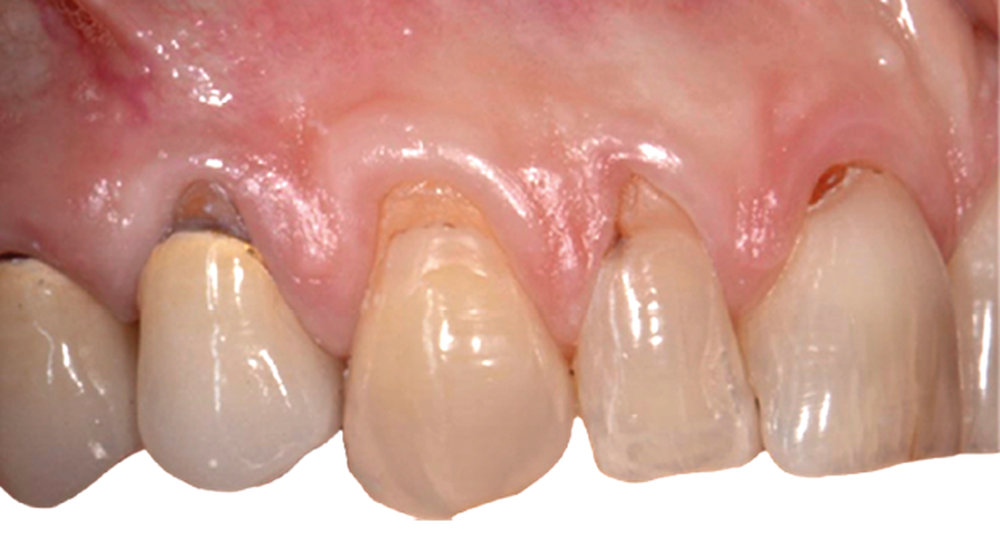

Le tracé d’incision papillaire, très précis, permet d’éviter les décharges. Il consiste à réaliser des incisions para-marginales obliques qui vont toutes être orientées en direction de la récession la plus sévère, ce qui permet d’obtenir un lambeau déplacé avec une légère rotation des papilles.

Le lambeau est ensuite décollé grâce à la méthode partielle-totale-partielle (« Split-Full-Split »). Les papilles chirurgicales sont décollées en épaisseur partielle afin d’obtenir un lit receveur et de stabiliser la position du lambeau au moment des sutures. Le lambeau est levé en pleine épaisseur jusqu’à la ligne de jonction muco-gingivale afin d’emporter le périoste, qui permet la vascularisation du lambeau. Enfin, dans un objectif de gain de laxité, le lambeau sera disséqué en demi-épaisseur dans la muqueuse alvéolaire. Cette dissection se fait en deux plans : un plan profond et un plan superficiel parallèle au lambeau muqueux. Le but est de permettre de repositionner le lambeau avec un minimum de tension.